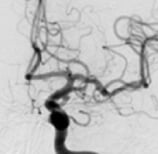

Angiografias em projeções frontal e perfil de um homem de 58 anos em investigação por cefaleia. O círculo mostra o aneurisma cerebral.

Angiografia projeção frontal após a cirurgia no cérebro para a clipagem do aneurisma cerebral.

Angiografia projeção perfil após a cirurgia no cérebro para a clipagem de aneurisma cerebral.